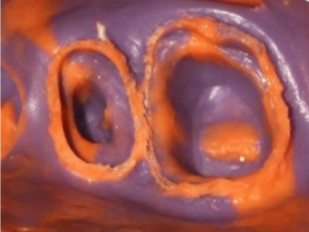

ステップ6: 正確な印象を取る

PERFITインプレッション製品を使用して、正確なインプレッションを取得します。 HUGEは、さまざまな粘度と硬化速度を備えた印象素材を提供します。

* 引き込みコードを使用した歯肉変位後の歯肉溝内の材料の流動性に注意してください。これにより、歯の周囲全体の優れたレプリカが実現します。